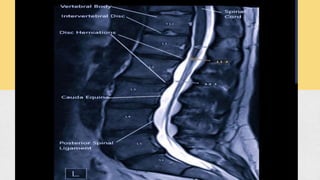

DIAGNOSIS.

● CT, MRI etc.

INTERVERTEBRAL DISC COMPONENTS. Itis the consists of three components. a. Cartilage end plates. b. Nucleus pulposus. c. Annulus fibrosis. The cartilage plates is thin layers of hyaline cartilage. That's adjacent vertibral bodies. The annulus palposus is a gelatinous material That's help in maintenance of pressure.

The nucleus displacementhas four type . 1. Stage of degeneration. (Due to the accumulation of the nuclear material and the stiffness) 1. Stage of protrusion .( Due to the entire thickness has disintegration and fragment the nuclear material) ● It is also called the disc bulge. 1. Stage of extrusion . (Due to the nuclear material out of the annulus and lies posterior longitudinal ligament. 1. Stage of sequestration ( it is a when the disc loose and nuclear material out of contact with the parent disc 3 STAGE OF FIBROSIS _ It is the residual nucleus pulposus becomes fibrosis. The commonests level of disc prolapses between( L4_L5), L4_L3 ,. ( C5_ C6 )

DIAGNOSIS. ● CT, MRIetc. CLINICAL FEATURES _ ● Age 20 to 40 years person. ● Low back pain. ● Sciatica pain. ● Cauda equina syndrome. EXAMINATION _ ● Posture. ● Movements. ● Tenderness. ● Straight leg line test ( SLRT) . ● Lasegue test. ● Neuro examination.